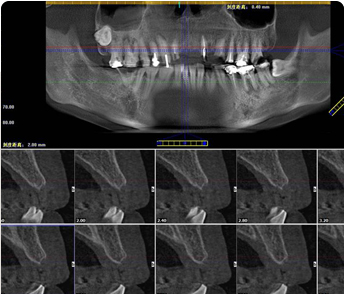

锥形束平板CT:

360°3D口腔透视

数字化3D导板定位植体深度、角度,微孔植入创口牙根大小